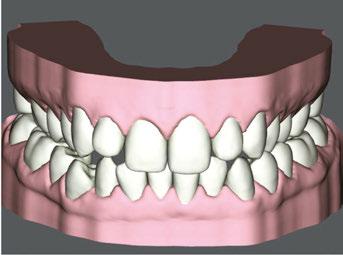

Treatment results

Upon completion of MFT and active treatment phase with clear aligners (Figures 12, 13, 14, 15, 16), the patient revealed that snoring significantly reduced, her partner does not complain anymore, and she is breathing through the nose 75% of the time. The patient is holding her lips together 75% of the time and is able to keep her tongue on the spot 50% of the time.

I recommendeded that the patient wear her retainers every night, continue with her MFT exercises, and have recall visits for MFT every 3 months to continue to improve her tongue strength, lip seal, and nose breathing capabilities.

Figure 12: Anterior view upon the completion of active treatment

Figure 17: Smile upon the completion of active treatment

Figures 13 and 14: 13. Right side upon the completion of active treatment. 14. Left side upon the completion of active treatment

Figures 15 and

15. Occlusal view upon the completion of active treatment. 16. Lower occlusal view upon the completion of active treatment